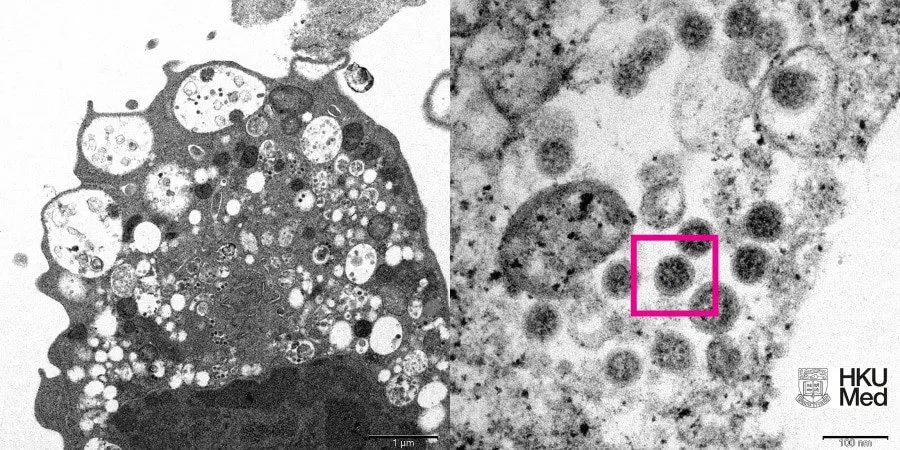

The photograph shows an electron micrograph of a monkey kidney cell (Vero E6) infected with an omicron. There is a picture at low and high magnification.

The picture shows lesions with swollen vesicles, which contain viral particles. At high magnification, the researchers were able to make out clusters of characteristic spherical objects with crown-shaped spikes on their surface.